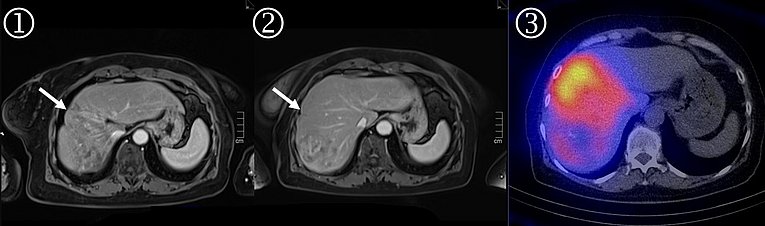

SIRT (selektive interne Radiotherapie)

Die SIRT ist eine relativ neue Behandlungsform von Lebertumoren, welche nicht einem lokalen Verfahren wie Operation oder Ablation zugeführt werden können. Hierbei werden mehrere Millionen radioaktiver Kügelchen (sogenannte „Mikrosphären“) über einen Gefäßzugang in der Leiste in den Tumor verbracht. In den kleinen Arterien des Tumors bleiben diese dann stecken und können über Tage hinweg radioaktive Strahlung an den Tumor abgeben. Da wie bereits erwähnt gesundes Lebergewebe vor allem durch portalvenöses Blutversorgt wird, wird gesundes Lebergewebe kaum beeinträchtigt.